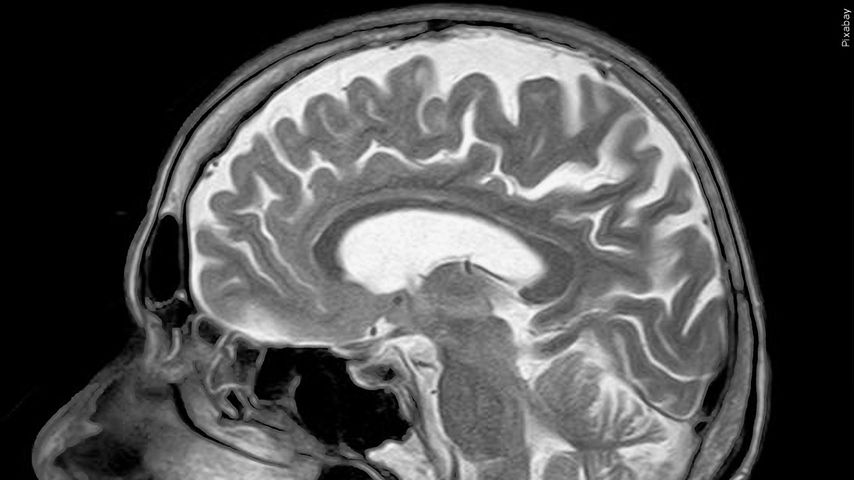

BATON ROUGE — Meningiomas are usually noncancerous tumors that form in the membranes surrounding the brain.

"We have what's called navigation so that allows us to use a pre-op MRI, sort of a GPS for the brain, to know exactly where the tumor is in relationship to the structures that we're trying to preserve and avoid," Clark said.